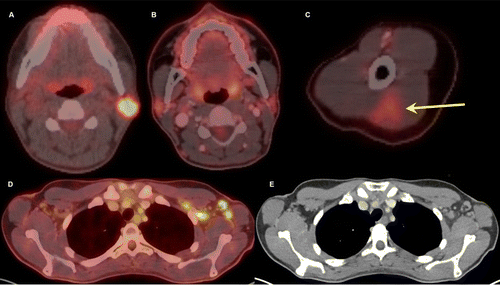

Thirty-two-year-old female. A, Axial fused 18-FDG PET/CT

showed hypermetabolic biopsy proven intraparotid lymph node with metastatic

malignant melanoma. B, Three-month follow-up axial fused 18-FDG PET/CT shows

complete resolution of the neck mass following chemotherapy, C, while left arm

shows hypermetabolic triangular shaped inflammation (arrow) at the COVID

vaccine injection site. D, Axial fused images at the axilla level shows

multiple new hypermetabolic lymph nodes. E, Axial contrast enhanced CT

demonstrates mild fat stranding surrounding the ovoid lymph nodes with

preserved fatty hilum.

Özütemiz et al, Radiology 2021 ©RSNA 2021